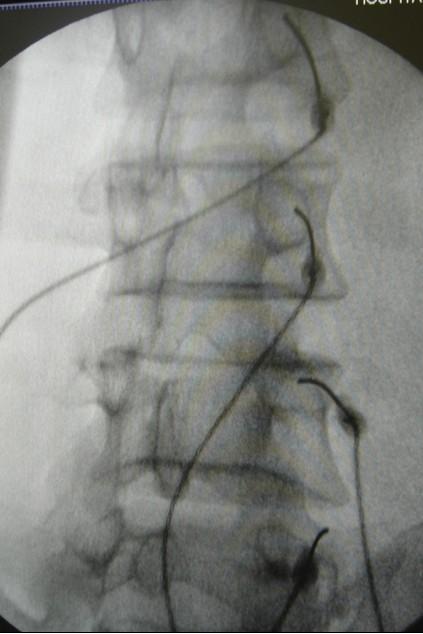

Para localização dos pontos exatos, utilizamos de fluoroscopia que, basicamente, é uma câmera de vídeo acoplada a um aparelho de raios-x, permitindo ao cirurgião ver exatamente o ponto de inserção das agulhas em tempo real, minimizando os riscos de lesões inadvertidas, tornando então o procedimento seguro.

Ao lado, mostra-se uma imagem de Raio-X com a correta colocação das agulhas na saída do ramo medial que deve ser confirmada antes de iniciar a lesão térmica.

O método de denervação da sacro-ilíaca é semelhante ao da região lombar. A diferença é a distribuição da inervação que é ampla, maior e mais difusa que nas facetas, necessitando denervarmos diversos pontos para um alívio satisfatório.